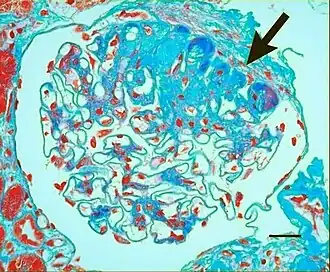

Light micrograph showing hypertensive glomerular lesion of hypertensive nephropathy: global glomerular collapse and filling of Bowman's space with a lightly staining collagenous material. -

Light micrograph showing signs of hypertensive nephropathy: interstitial fibrosis, tubular atrophy with thickened tubular basement membranes, and fibrous intimal thickening of a small artery (arrow).